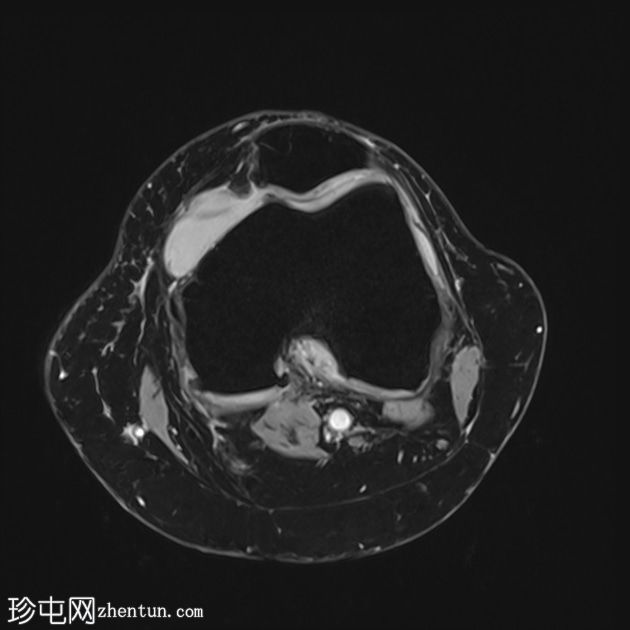

轴位质子密度加权像 (PD)

脂肪抑制像

轴位T2加权三维增强像 (T2-ME3D-WE)

前交叉韧带 (ACL) 呈增厚的高信号,提示黏液样变性。然而,纤维仍保持连续性,在矢状位质子密度加权像上尤为明显。这种特征性表现类似于芹菜,因此被称为“芹菜茎征”。

内侧半月板后角显示异常信号,延伸至关节面下方,符合3级撕裂。

髌股关节和胫股关节均可见骨关节炎改变,表现为骨赘形成、胫骨棘突增生以及关节软骨在相对关节面上的剥脱。

可见少量滑液积液,滑液内可见髌上皱襞。

内侧副韧带可见异常水肿信号,但未见纤维断裂,提示为I级扭伤。

此外,胫股关节胫骨髁间区可见局灶性软骨变薄,伴有骨暴露和骨髓水肿。

该病例的特征为前交叉韧带黏液样变性。此外,还有退行性关节病伴轻度关节积液,以及髌上皱襞撕裂和内侧副韧带扭伤。